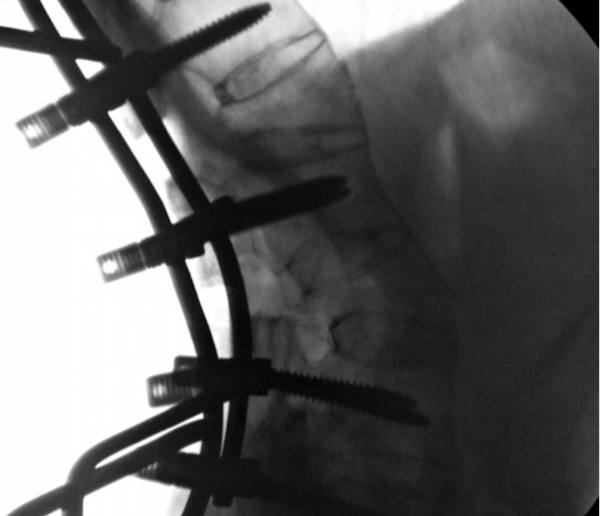

复位完成后术中透视

术后复查